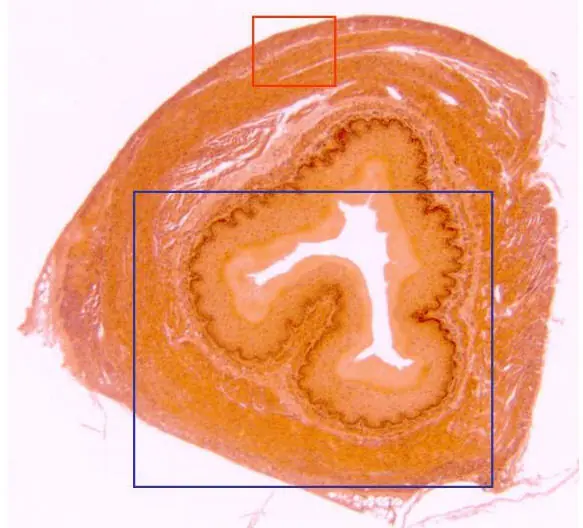

dijo:Sección transversal de una arteria elástica, teñida con hematoxilina/eosina y observada con el objetivo de 10x. Se distinguen las tres capas que la integran, de fuera a dentro: adventicia, media e íntima, ésta última en contacto con la luz del órgano.

dijo:Con el objetivo de 40x se distinguen las tres capas: adventicia, media e íntima (ésta última en torno a la luz) de la arteria. En otra microfotografía se aprecia un detalle de las dos primeras (rojo)

dijo:Con el objetivo de 100x se distinguen con detalle las capas íntima (en contacto con la luz) y media de la arteria. La primera, constituida por un endotelio, descansa sobre una lámina elástica. Por debajo (hacia el exterior del órgano) se localiza la capa media, formada por numerosas láminas elásticas, fibras musculares lisas y fibroblastos